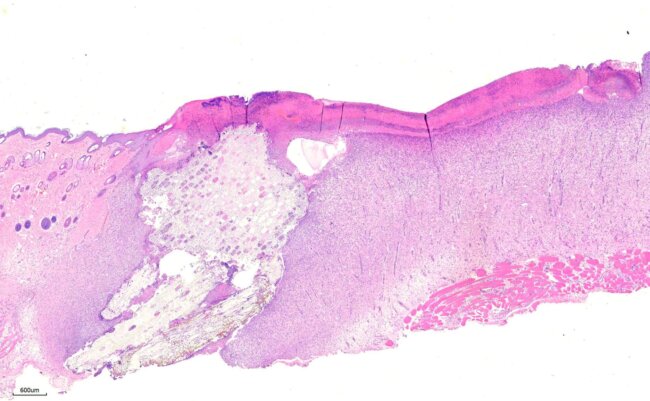

皮膚傷口敷料